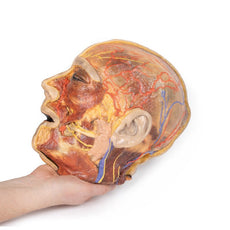

The face: On the right side of the head the parotid gland has been removed to reveal the facial nerve and all its branches (temporal, zygomatic, buccal, marginal mandibular and cervical) and demonstrate the spatial relations of structures embedded in the gland from superficial to deep (facial nerve, retromandibular vein, external carotid artery). In the surrounding region the temporalis, masseter and posterior belly of digastric are exposed, as are and the facial artery, transverse facial artery and superficial temporal artery. The facial vein and transverse facial vein are clearly visible uniting to form the common facial vein which is joined by the retromandibular vein to form the external jugular vein.

Viewed from the anterior aspect the face has been dissected to display some of the facial muscles around the mouth (buccinator [on the left], orbicularis oris and zygomaticus major). On the left side of the infratemporal fossa has been open to expose the medial and lateral pterygoids.

The lateral pterygoid is divided to show the mandibular division of the trigeminal nerve dividing into the lingual nerve and the inferior alveolar branch. Also on the left side the branches of the ophthalmic division of the trigeminal that supply the skin above the eyebrows and scalp (supraorbital [left only] and supratrochlear nerves [both sides]) are dissected. The submandibular gland is clearly visible below the mandible on both sides as are the facial arteries and veins as they course over the mandible.

This 3D print specimen preserves a series of features of the head and visceral column of the neck:The face: On the right side of the head the parotid gland has been removed to reveal the facial nerve and all its branches (temporal, zygomatic, buccal, marginal mandibular and cervical) and demonstrate the spatial relations of structures embedded in the gland from superficial to deep (facial nerve, retromandibular vein, external carotid artery). In the surrounding region the temporalis, masseter and posterior belly of digastric are exposed, as are and the facial artery, transverse facial artery and superficial temporal artery. The facial vein and transverse facial vein are clearly visible uniting to form the common facial vein which is joined by the retromandibular vein to form the external jugular vein.

Viewed from the anterior aspect the face has been dissected to display some of the facial muscles around the mouth (buccinator [on the left], orbicularis oris and zygomaticus major). On the left side of the infratemporal fossa has been open to expose the medial and lateral pterygoids.

The lateral pterygoid is divided to show the mandibular division of the trigeminal nerve dividing into the lingual nerve and the inferior alveolar branch. Also on the left side the branches of the ophthalmic division of the trigeminal that supply the skin above the eyebrows and scalp (supraorbital [left only] and supratrochlear nerves [both sides]) are dissected. The submandibular gland is clearly visible below the mandible on both sides as are the facial arteries and veins as they course over the mandible.